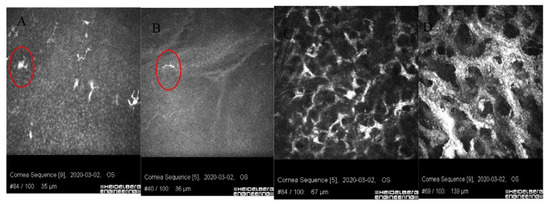

- Mazzotta, C.; Hafezi, F.; Kymionis, G.; Caragiuli, S.; Jacob, S.; Traversi, C.; Barabino, S.; Randleman, J.B. In Vivo Confocal Microscopy after Corneal Collagen Crosslinking. Ocul. Surf. 2015, 13, 298–314. [Google Scholar] [CrossRef] [PubMed]